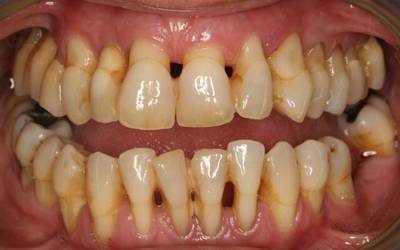

Хронический генерализованный

Характеризуется патологическими изменениями всего зубного ряда или всех зубов. Последствия такой формы — частичное или полное выпадение зубов.

Начинается заболевание с кровоточивости десен. Затем появляется зуд и жжение, пародонтальные карманы углубляются, расстояние между зубами увеличивается.

Нередко зуб начинает заваливаться, прикрывая собой другой, находящийся рядом. Подвижность зубов и обнажение корней проявляется с увеличением тяжести заболевания.

Причины возникновения — зубной камень или местные раздражители (брекеты, виниры, неправильно поставленная пломба, острые края зубов).